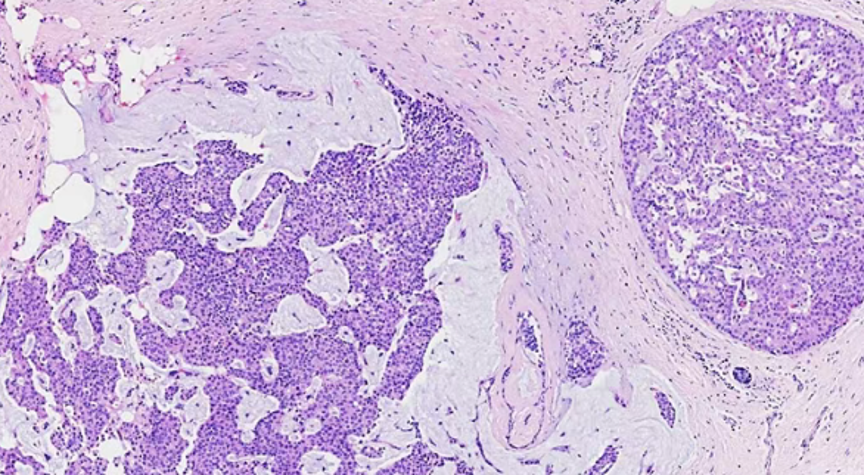

2、实性乳头状癌伴浸润:轮廓圆滑的结节,伴有浸润性成分,包括粘液癌,NET,浸润性癌(NST)

SPC+富于细胞的黏液癌

最终诊断:浸润性实性乳头状癌,部分为粘液癌。